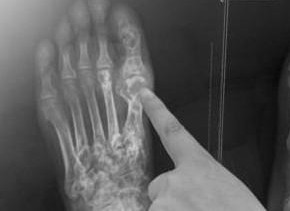

痛風(fēng)是一種因高尿酸血癥導(dǎo)致的關(guān)節(jié)炎癥,常表現(xiàn)為關(guān)節(jié)紅腫熱痛,嚴(yán)重影響患者的生活質(zhì)量,隨著現(xiàn)代生活方式的改變,痛風(fēng)患者日益增多,尋找有效的治療方法顯得尤為重要,本文旨在探討治療痛風(fēng)的最佳方法,幫助患者早日擺脫病痛。

治療痛風(fēng)的最佳方法包括:調(diào)整飲食,避免高嘌呤食物,保持充足的水分?jǐn)z入;藥物治療,使用非處方藥物緩解疼痛和消炎,或在醫(yī)生指導(dǎo)下使用處方藥降低尿酸水平;生活方式改變,如定期運(yùn)動(dòng)、戒煙和限制酒精攝入等。綜合這些方法能有效控制痛風(fēng)癥狀,預(yù)防其發(fā)作。